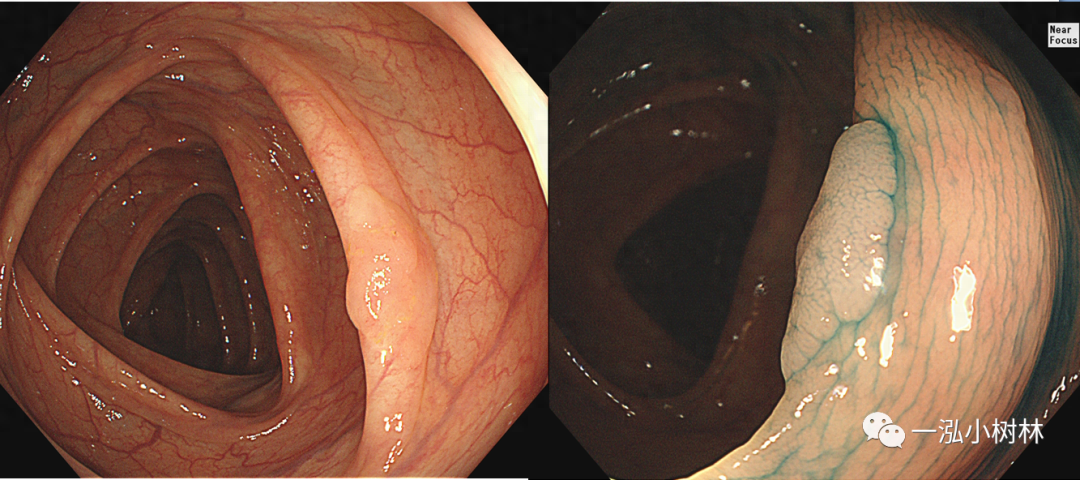

图2 结肠管状腺瘤(Pit Pattern IIIL型)

图3 结肠管状腺瘤(Pit Pattern IIIL型)